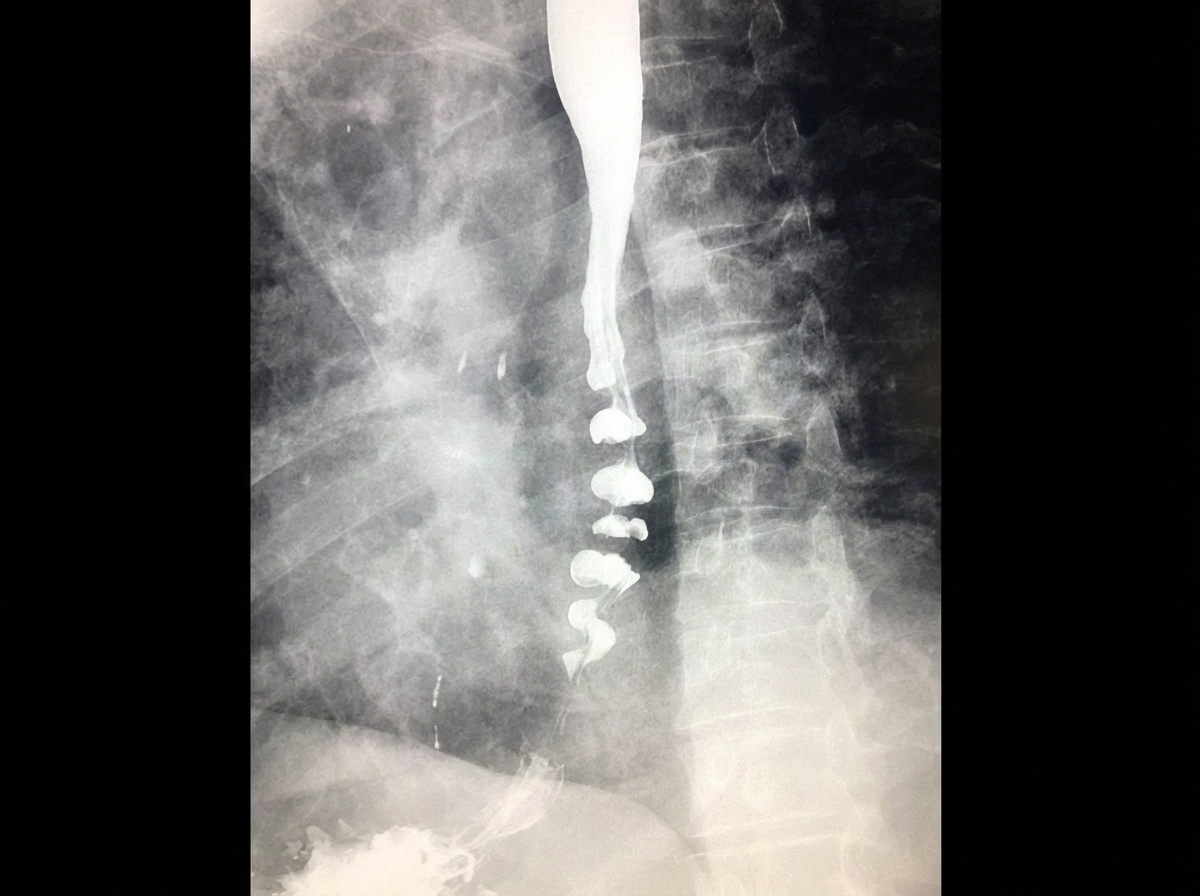

A 64-year-old Caucasian male presents to the cardiologist complaining of chest pain. He describes the pain as spontaneous and radiating to his back, ears, and neck. He denies dyspnea on exertion. The patient is referred for an upper GI barium swallow, shown in image A. Which of the following would you most expect to find during further workup of this patient?